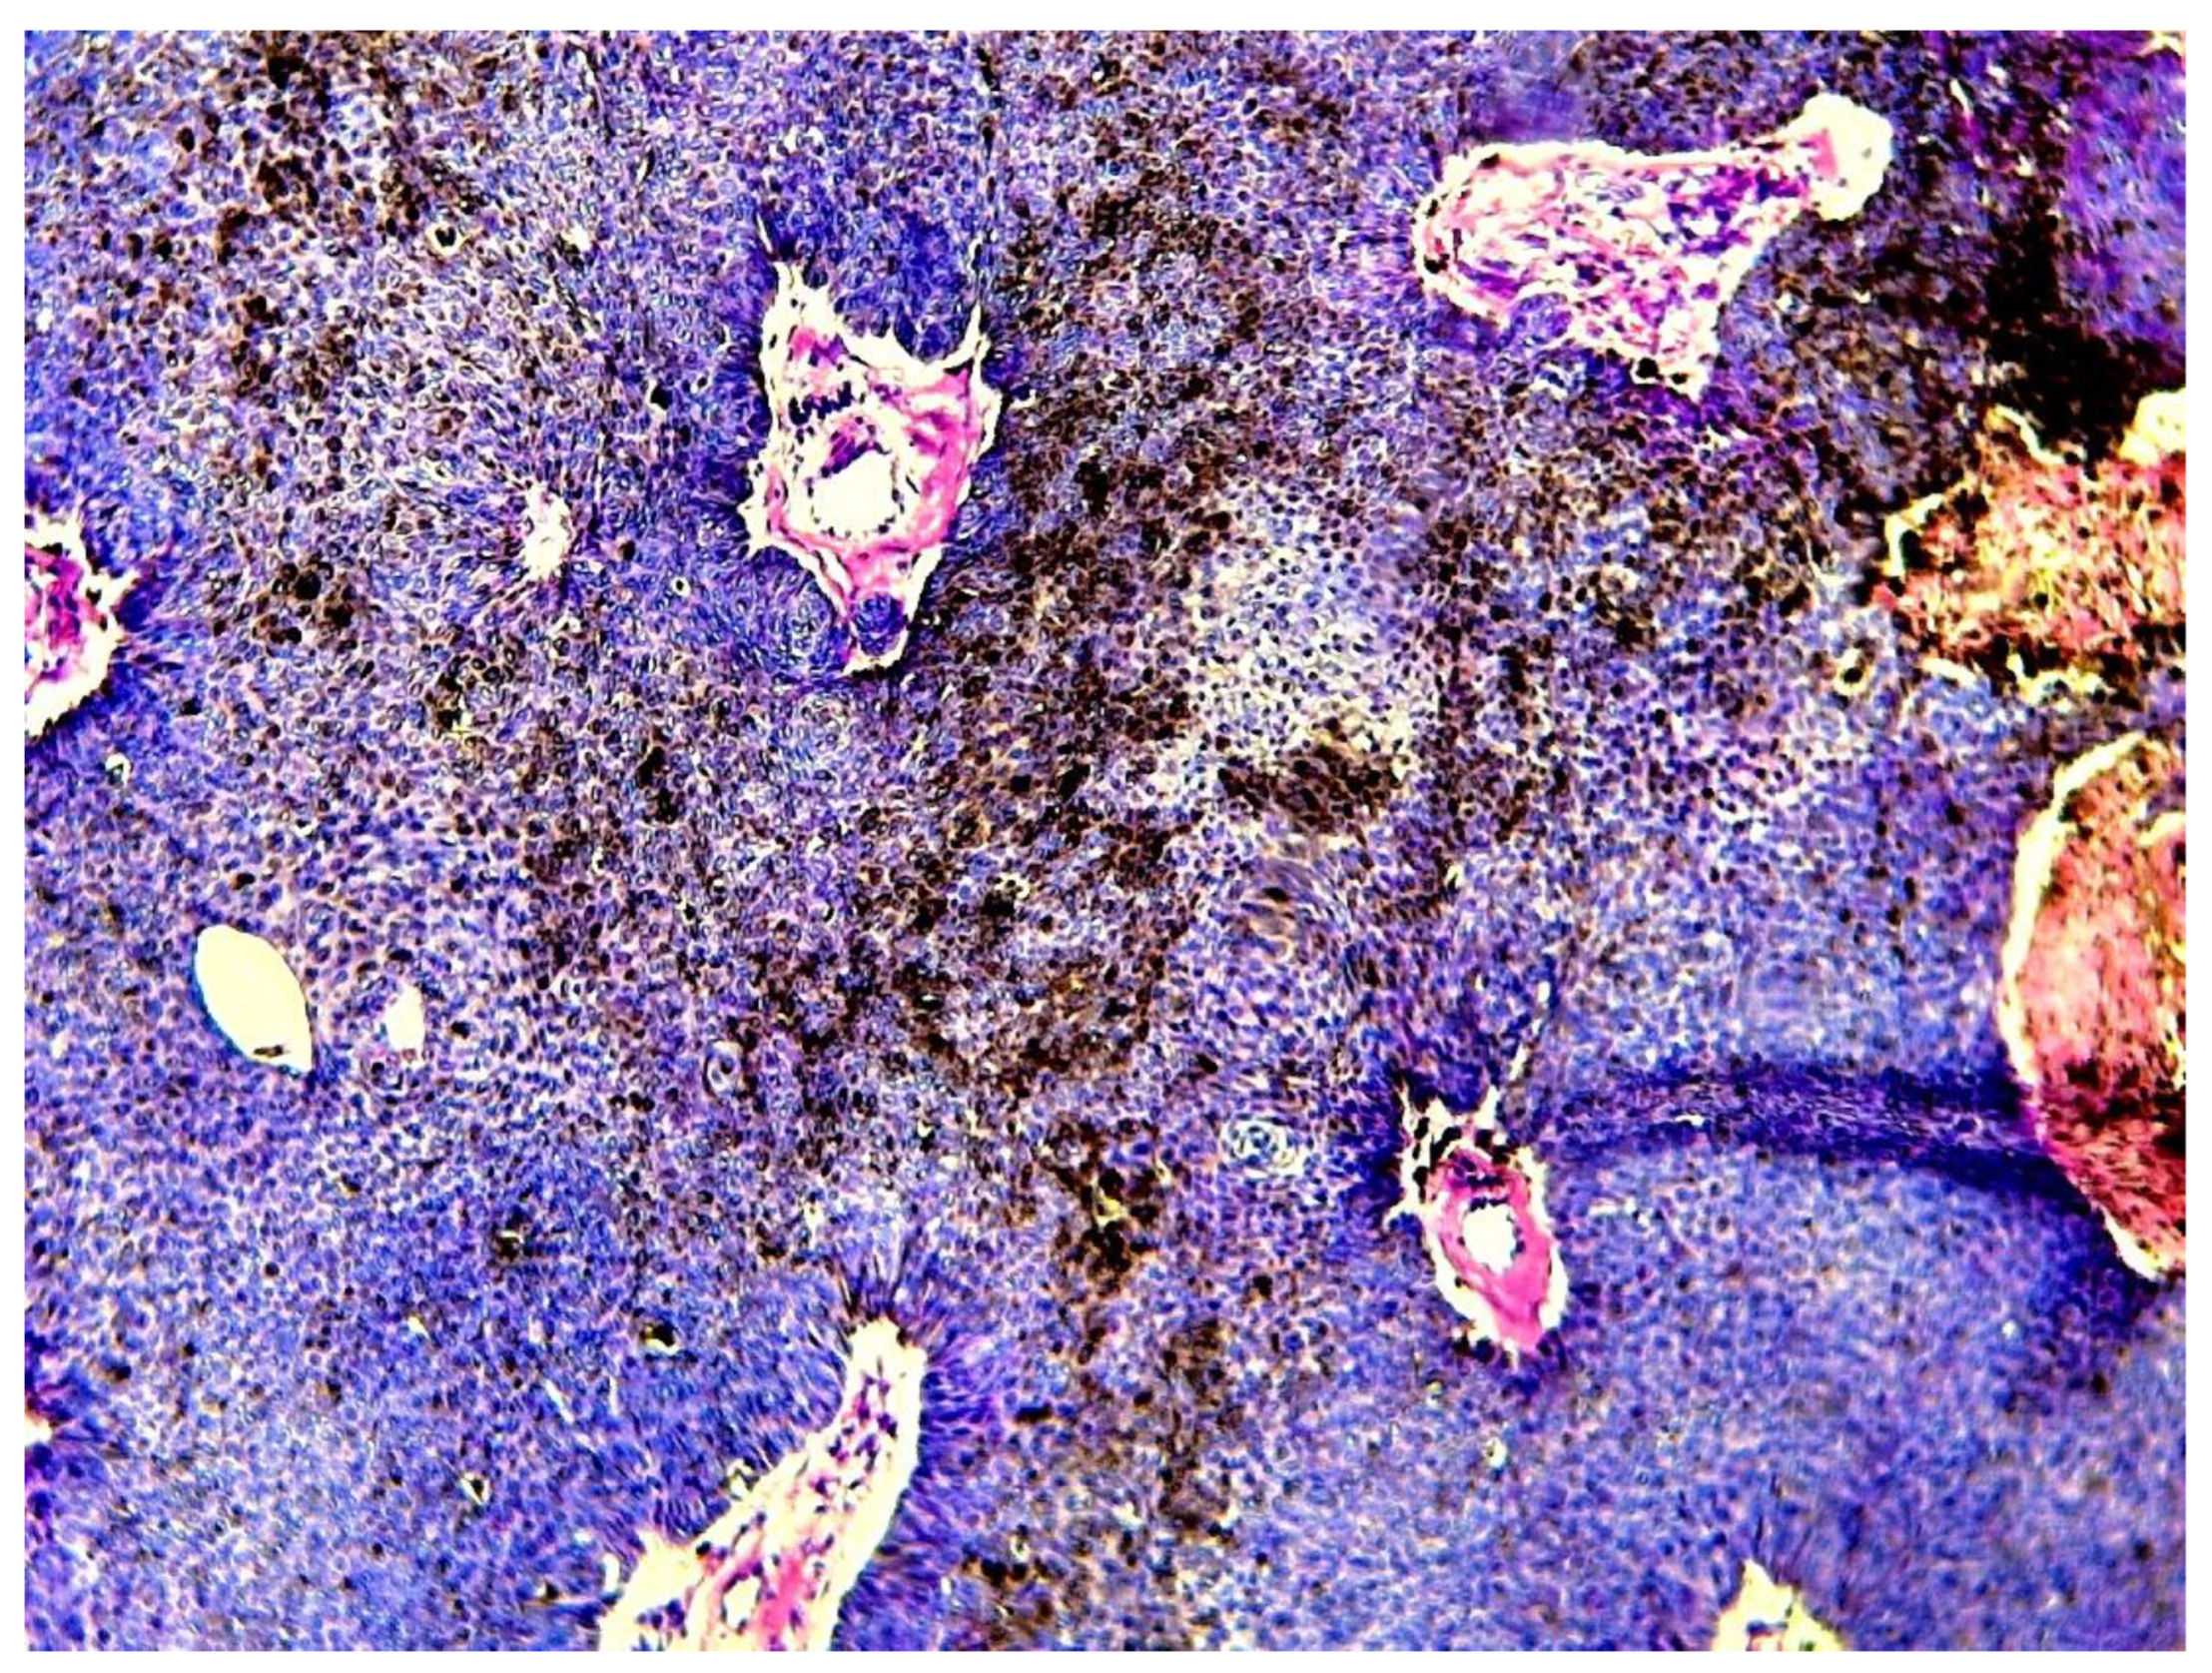

All cases were made of a variable mixture of poroid (uniform small cuboidal cells with round nuclei) and cuticular cells (larger cells with abundant eosinophilic cytoplasm), without cellular atypias, mitoses or stromal infiltration. The tumors’ stroma was fibro-hyaline and inflammatory in all cases, sometimes loose and myxoid. A broad epidermal connexion was observed in all cases of CP, whereas absent in cases of PH (cases 6 and 9) and DDT (case 12). Clear cells were observed in 7 cases (53.8%) (Figure 3).

Figure 3. Histological image showing large areas of clear cell changes with abundant clear cytoplasm (hematoxylin-eosin x 200) (case 2).